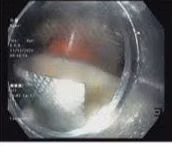

Các bác sĩ tại Bệnh viện Nhân dân Gia Định vừa thực hiện thành công ca nội soi, gắp dị vật vỏ thuốc cho người bệnh D.H.L, 18 tuổi, ngụ tại quận Bình Thạnh, TP HCM. Người bệnh cần thận trọng khi uống thuốc để tránh nhập viện cấp cứu.